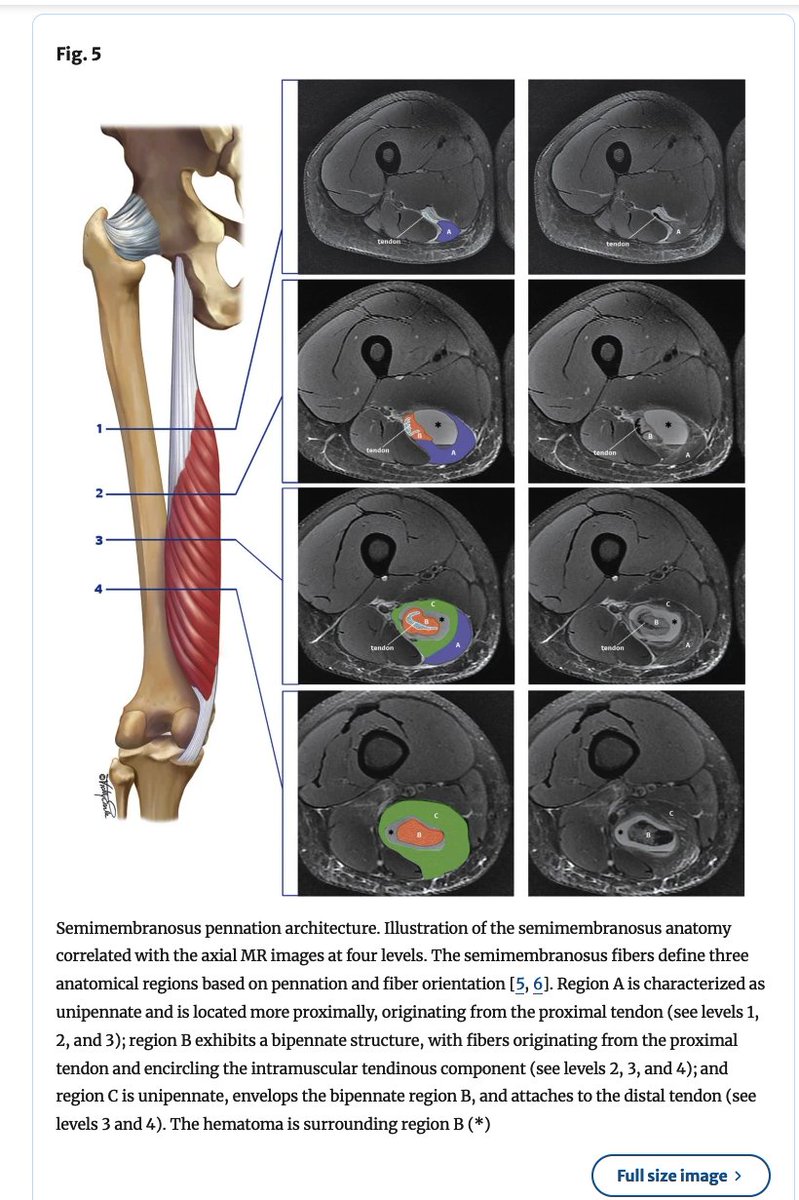

⚽️Degloving intramuscular injuries of the semimembranosus and adductor longus muscles in adolescent soccer players... Degloving muscle injury was described for the rectus femoris where the inner bipennate component is dissociated from its superficial unipennate component. The